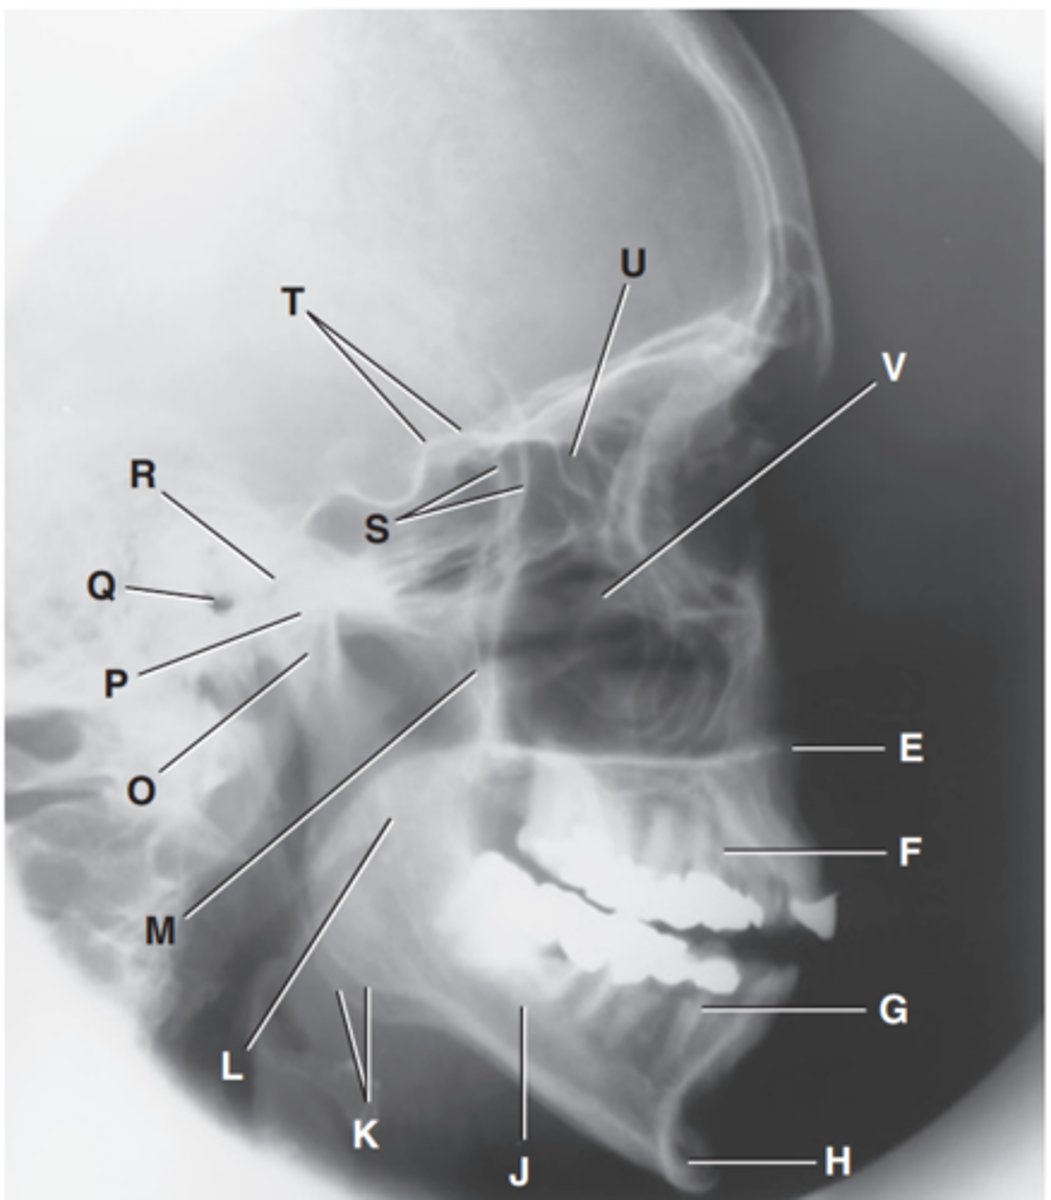

Zygomatic arch

Label A

Right zygomatic bone

Label B

Right nasal bone

Label C

Frontal process of right maxilla

Label D

Anterior nasal spine

Label E

Alveolar process of maxilla

Label F

Alveolar process of mandible

Label G

Mentum or mental protuberance

Label H

Mental foramen

Label I

Body of mandible

Label J

Angle (gonion)

Label K

Ramus of mandible

Label L

Coronoid process

Label M

Mandibular notch

Label N

Neck of mandibular condyle

Label o

Condyle or head of mandible

Label P

EAM

Label Q

TM fossa of temporal bone

Label R

Greater wings of sphenoid

Label S

Lesser wings of sphenoid with anterior clinoid processes

Label T

Ethmoid sinuses between orbits

Label U

Body of maxilla containing maxillary sunuses

Label V